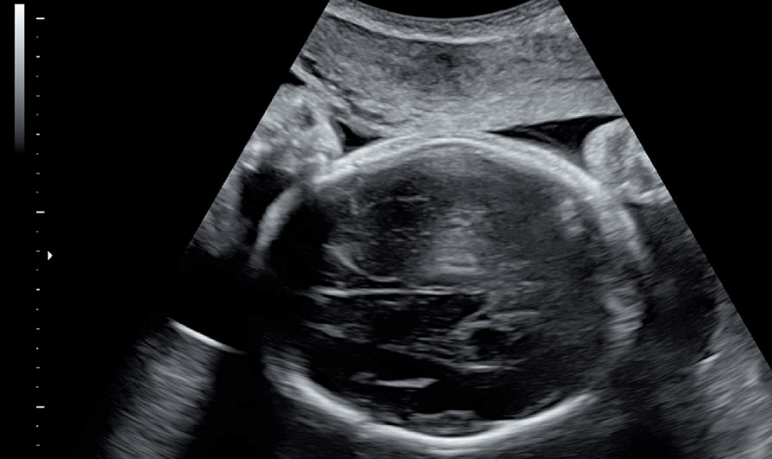

孕囊发育正常就会出现胚芽、胎血管博动及卵黄囊,是胚胎组织发育正常的表现,孕囊三个数据是代表孕囊大小,代表长、宽及厚,孕囊形状大多数是椭圆形,我们在B超上看到的是一个平面影像,但是实际上孕囊是立体的,所以会有三个径线,分别是长、宽、高。